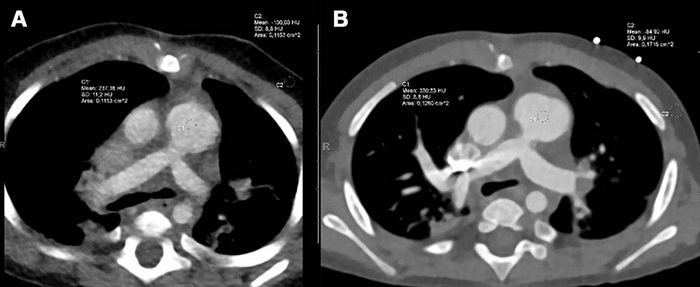

PCCT is an emerging imaging technique that counts the exact number and measures the energy of incoming x-ray photons. Compared with DSCT technology, PCCT offers higher image resolution and/or reduced radiation doses, which is of particular interest when imaging children. The PCCT technique has already been shown to improve cardiovascular CT imaging in adults. However, data on neonates and small children are lacking.

The researchers found that the PCCT images were sharper, with less image noise and greater contrast than DSCT images. The mean overall visual image quality ratings were higher for PCCT versus DSCT at a similar radiation dose. More than 97% of the PCCT images were at least diagnostic quality, compared to 77% of the DSCT images.

He noted that of the DSCT images, almost one-quarter were of limited or non-diagnostic quality, and 40% were of moderate quality.